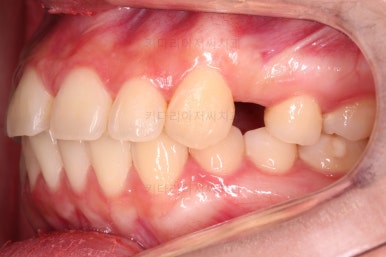

초진 시 입안의 모습을 보실게요.

결국은 앞니 사이에 틈이 생겼기 때문에 이같은 문제점을 인지하시고 내원하셨던거죠.

이번 환자분의 경우는 치아 결손 부위의 잇몸뼈도 양호했고 공간도 그리 크진 않았으며 윗니는 갯수가 1개 부족해도 교합을 맞추는데 문제가 거의 없기 때문에 시간이 좀 더 들더라도 임플란트 없이 앞니 사이 틈과 결손부위 틈새를 모아보기로 했어요.